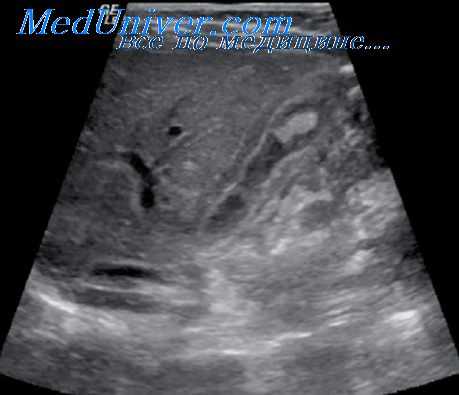

(Левый) На поперечном УЗ срезе брюшной полости визуализируется гетерогенная гипоэхогенная поджелудочная железа, что соответствует картине интерстициального отечного панкреатита. Спереди от тела поджелудочной железы определяется ги-поэхогенная перипанкреатическая жидкость, соответствующая острому скоплению секрета поджелудочной железы.